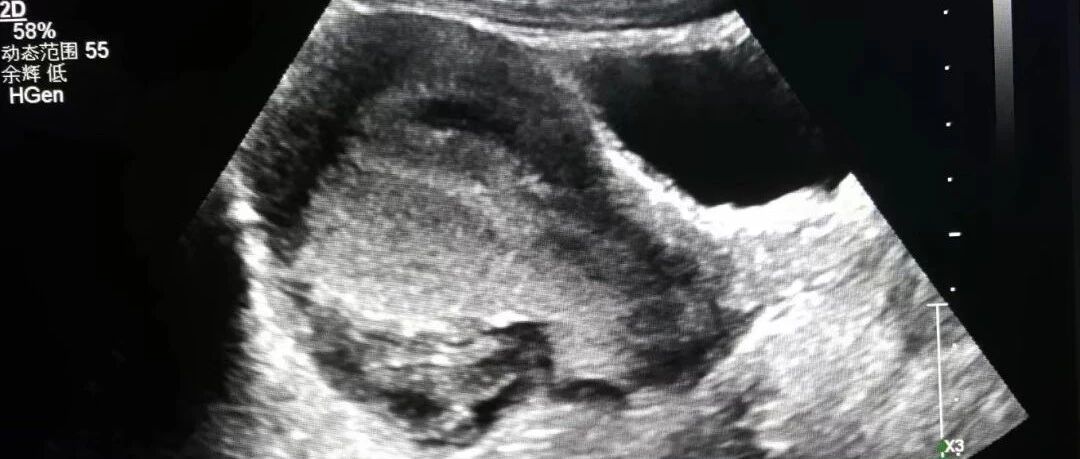

经典病例:遇到这样的胃窦癌,你能确诊吗? 丁香园超声时间 · 公众号 · 医学 · 1 年前 · |